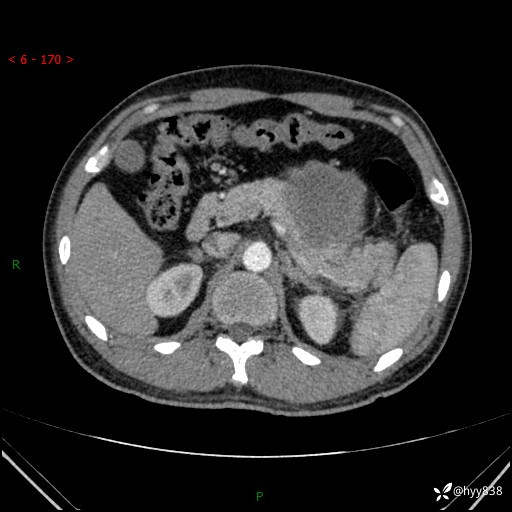

病例39岁/女,左侧腰痛入院。腹腔囊实性肿块,定位、定性---结果公布~

性别:男

年龄:39岁

简要病史:左侧腰痛待查,CT发现腹腔占位

腹部CT平扫+增强